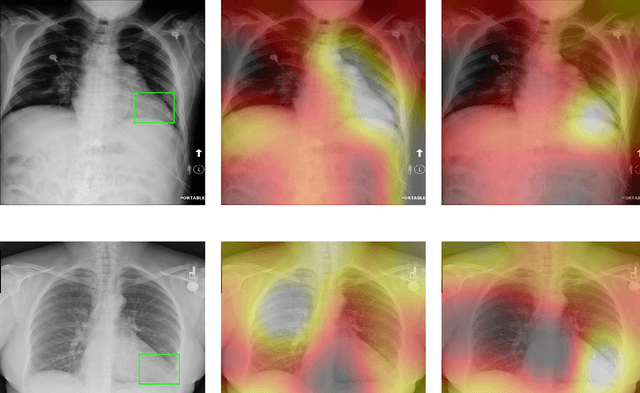

Deep Learning has thrived on the emergence of biomedical big data. However, medical datasets acquired at different institutions have inherent bias caused by various confounding factors such as operation policies, machine protocols, treatment preference and etc. As the result, models trained on one dataset, regardless of volume, cannot be confidently utilized for the others. In this study, we investigated model robustness to dataset bias using three large-scale Chest X-ray datasets: first, we assessed the dataset bias using vanilla training baseline; second, we proposed a novel multi-source domain generalization model by (a) designing a new bias-regularized loss function; and (b) synthesizing new data for domain augmentation. We showed that our model significantly outperformed the baseline and other approaches on data from unseen domain in terms of accuracy and various bias measures, without retraining or finetuning. Our method is generally applicable to other biomedical data, providing new algorithms for training models robust to bias for big data analysis and applications. Demo training code is publicly available.